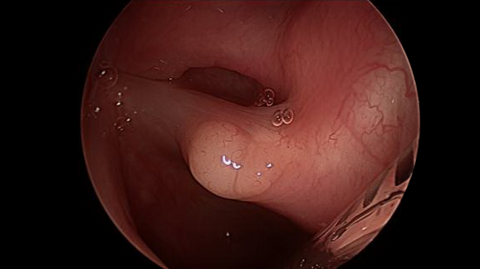

Fiberoptic Transnasal Laryngoscopy Showed a smooth yellow lesion on the dorsal surface of the right vocal process; laryngoscopy also showed abundant of lymphoid tissue in the adenoid fossa.

Preoperative Images